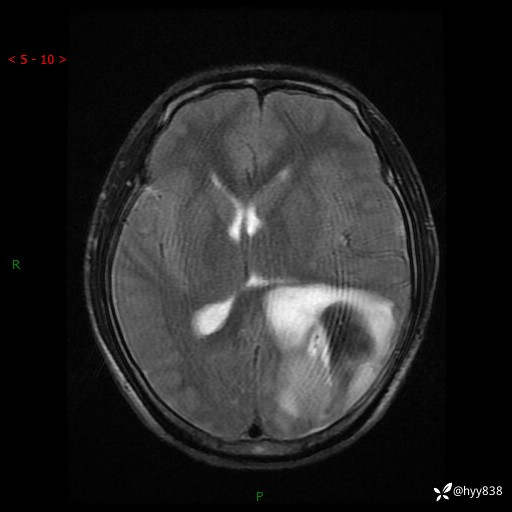

性别:男

年龄:21岁

简要病史:头痛伴呕吐半年,渐进性加重1月

颅脑MRI平扫+增强